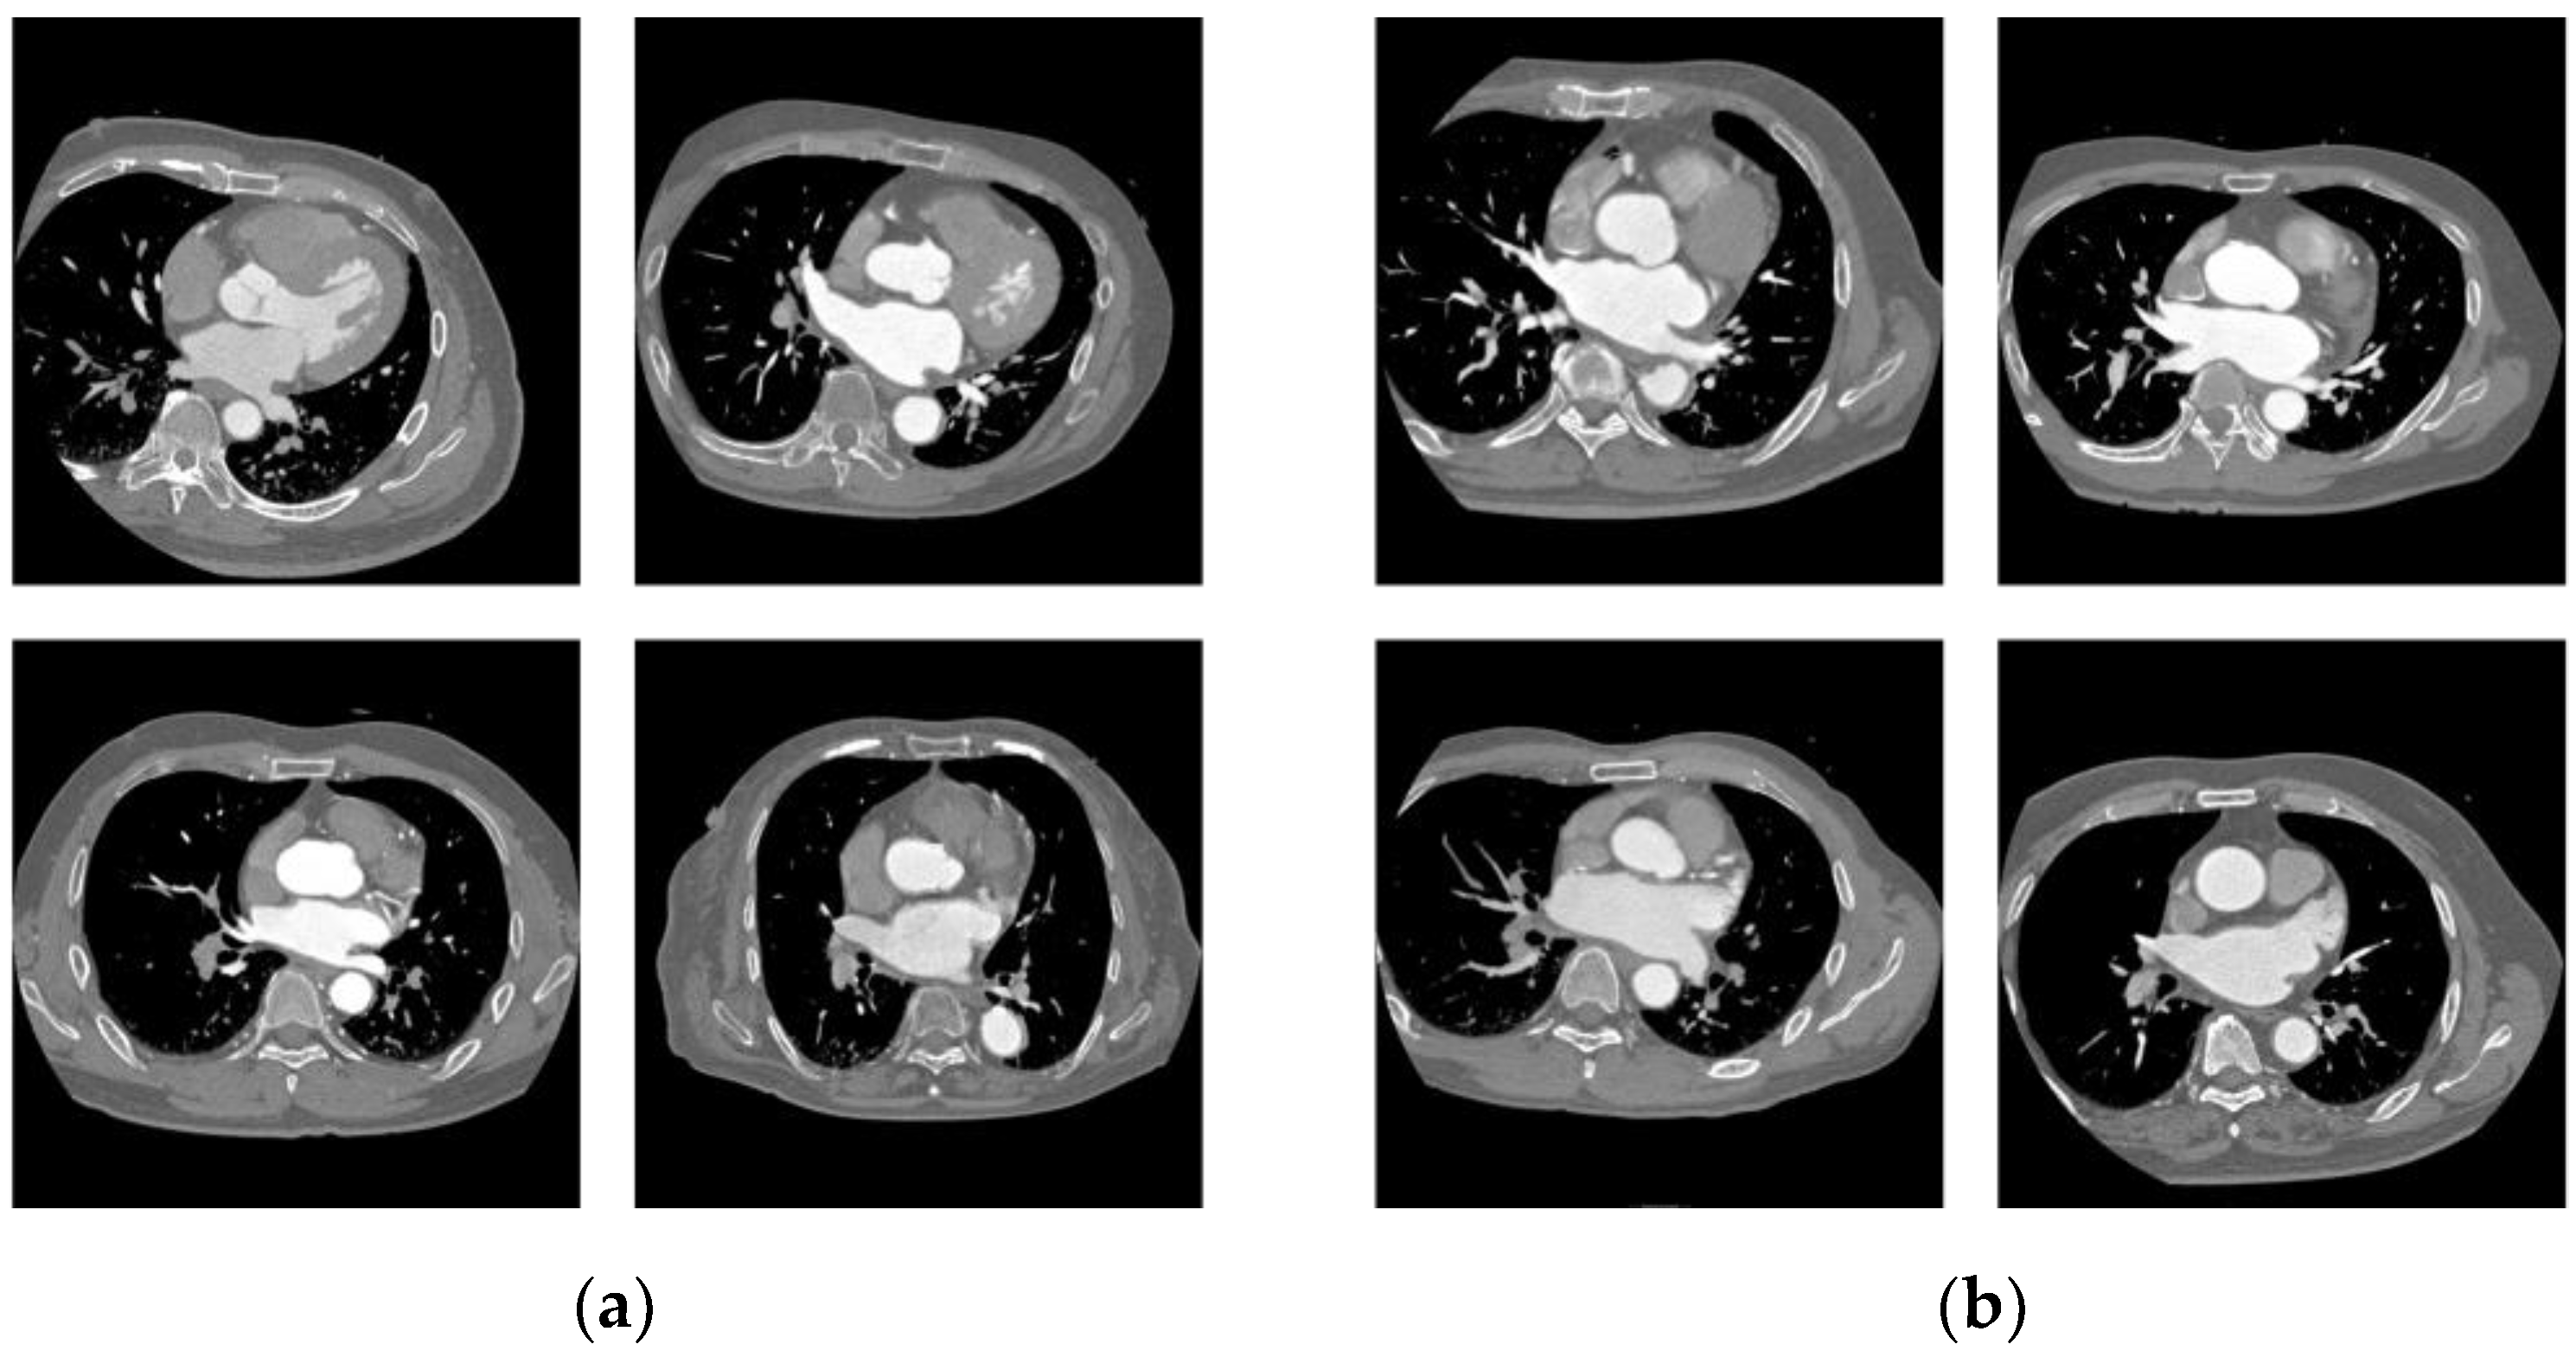

The images that were correctly classified by ResNet50 are shown in Figure 7, and those that were incorrectly classified are shown in Figure 8.

Figure 8.

Incorrectly classified cases. (a) PAF; (b) LSAF.

4.2. Insights from Saliency Map in CNN Classifications

Score-CAM was used to output a color map showing the pixels contributing to the CNN classification results. In the heatmap output for the correct classification in Figure 8, the left atrium and pulmonary veins tended to attract more CNN attention. In addition, when attention was focused on structures other than the heart, which was often seen in the heatmap output when the patient was incorrectly classified, as shown in Figure 10, there was a tendency toward incorrect classification. Focusing on the left atrium, cases of PAF were misclassified with findings of major LSAF, including an enlarged left atrium, the loss of comb-like muscular structures, and large rounded anterior and posterior structural left atria. In the cases of LSAF, there was also a tendency to misclassify cases in which the left atrium was not enlarged, especially when the anteroposterior diameter of the left atrium was short. Based on these findings, CNN classification focuses on the shape and surrounding structures of the left atrium and is considered a valid classification for the findings of LSAF.